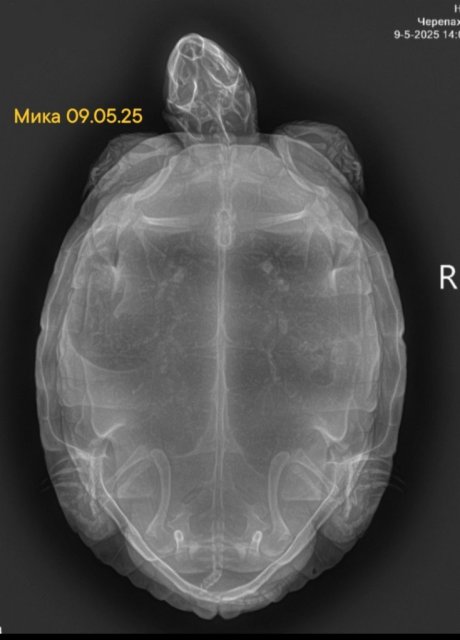

Спасибо за ответ, сделали простой рентген. Решено было делать  Рентген с контрастом или кт если не поможет лечение 7 ми дневное, т.к. кал немного да выходит, и аппетит дикошарый, активность сегодня появилась, на приеме шипела, убегала и за палец меня тяпнула нормально так)))

Черепаха Мика 19.05 покакала с кровью. Сделали сегодня УЗИ брюшной полости, инородных предметов в кишечнике и в области клоаки не выявлено. В рационе за последние полтора года 70% рептамин, 1-2 раза в месяц речная рыба (живцы),  раз в пару месяцев консервированные тараканы и чёрная львинка. Раз в месяц сепия очищенная.

В целом черепаха активная, аппетит прожорливый. В стадии фолликулогинеза. Специалист проводивший УЗИ сказала, что есть воспаление кишечника и скопление жидкости в брюшной полости, может вдруг знаете, из-за чего это могло произойти и какая дальнейшая перспектива?